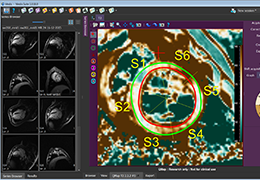

ANYTHINK 经导管主动脉瓣膜置换术分析系统